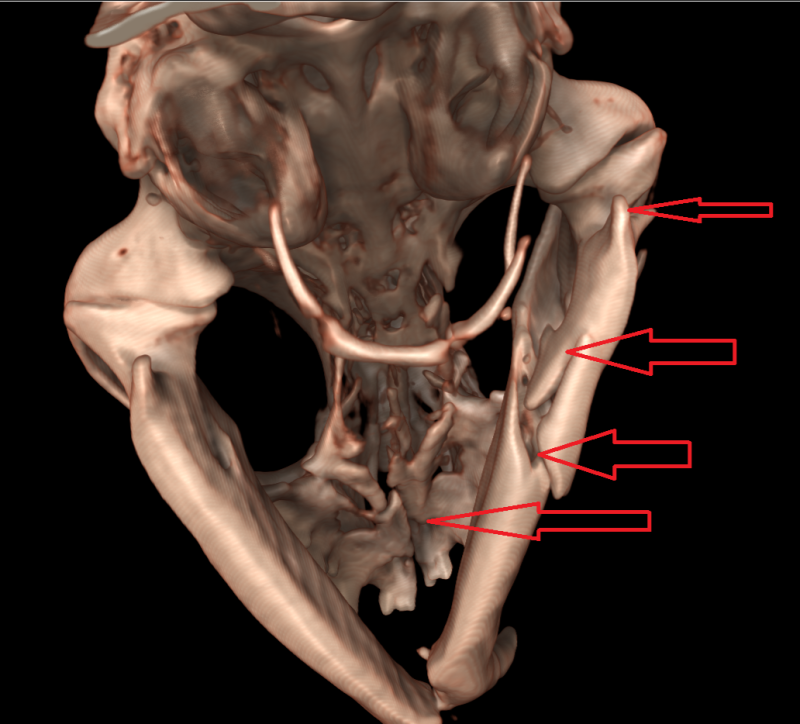

3D beeld van kop van kat met 9 breuken